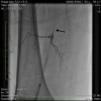

An angiogram from the left femoral sheath at this time showed retrograde filling of the distal and proximal SFA (Figure 4) and then the dissection plane in the EIA with a wire tip perforation and bleeding (Figures 5 and 6) to the retroperitoneal region at the external iliac artery with displaced bladder (Figure 6). Protamine was given to reverse the heparin and a 7-minute balloon inflation was performed in the distal SFA using a 5.0 mm×40 mm Evercross balloon (ev3, Plymouth, MN) to stop the retrograde bleeding. On repeat angiography, the distal SFA CTO was reoccluded and the dissection plane appeared to be sealed, with no further bleeding into the retroperitoneal region (Figures 7 and 8). Other than mild nausea after protamine, the patient reported no major symptoms during this procedure. When activated coagulation time was 130 s, the femoral and popliteal sheaths were removed. A 3-g/dl drop in hemoglobin was noted after the procedure that remained stable over the next two days. Popliteal and pedal pulses were palpable and unchanged following the procedure.